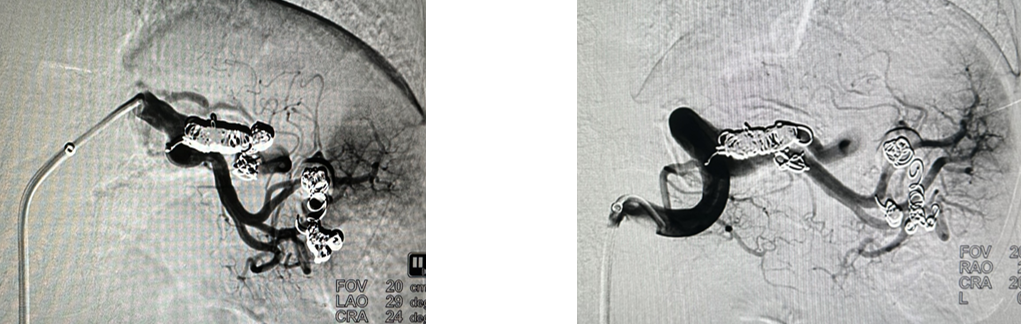

病例5 多发动脉瘤分支+主干栓塞

图为:分支栓塞

图为:主干栓塞最后造影